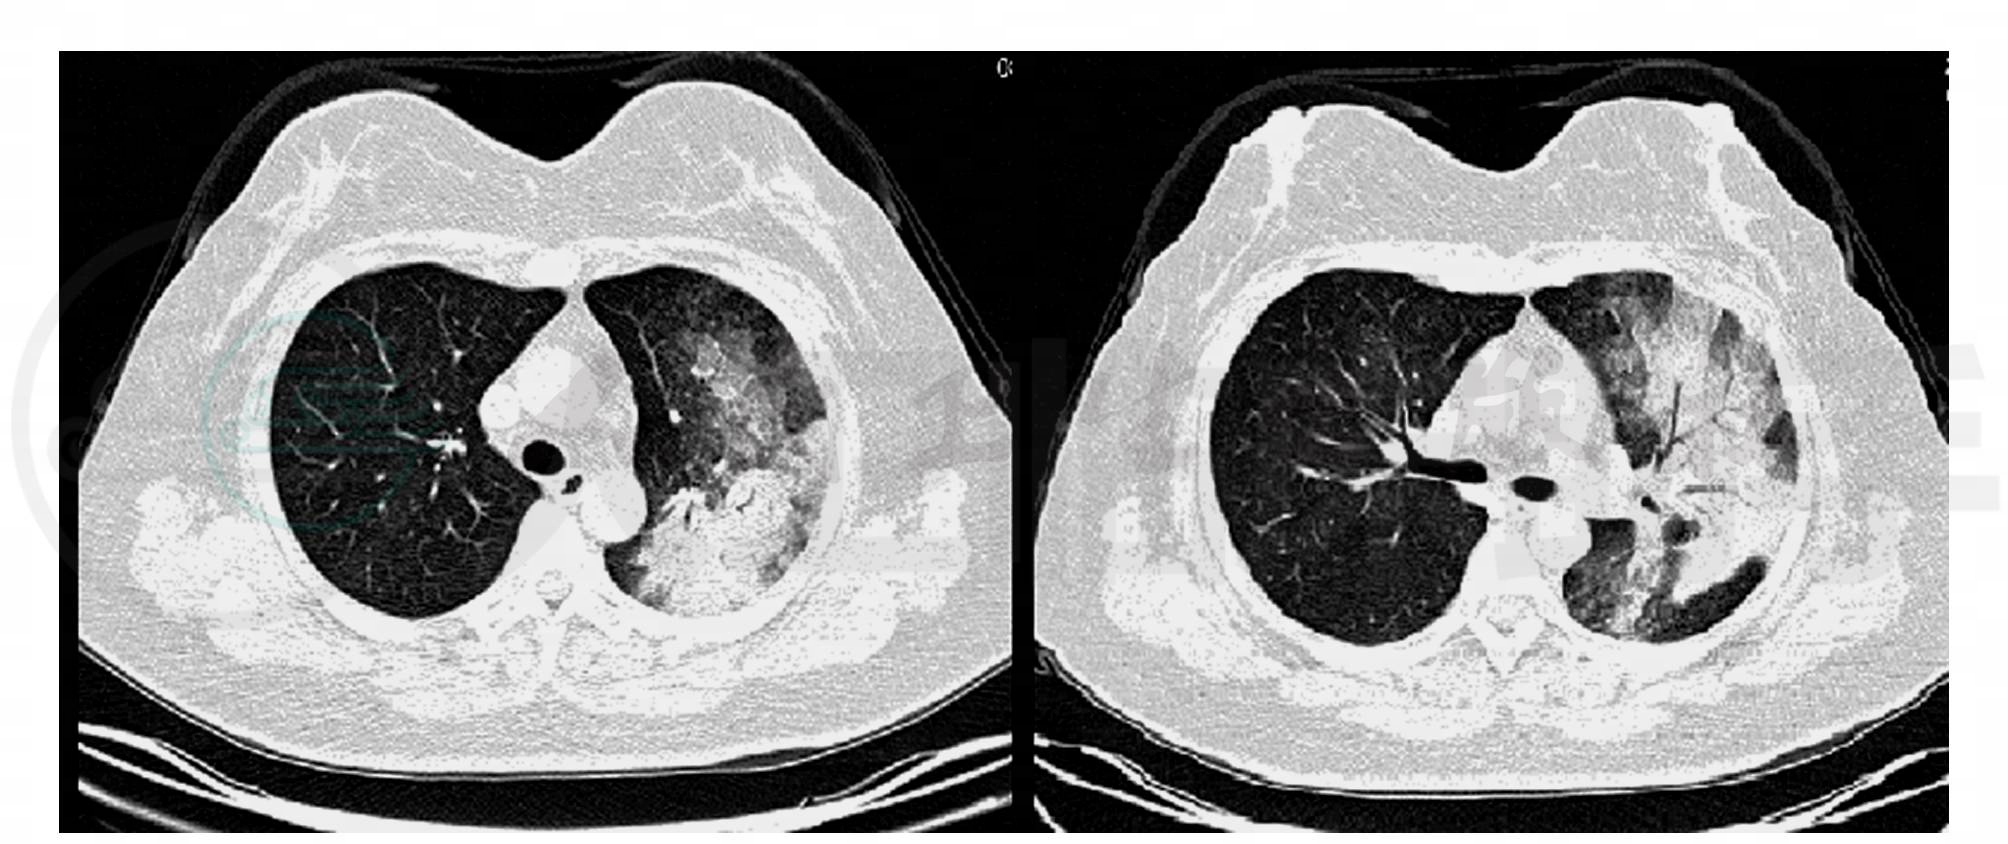

入院时辅助检查:血常规WBC 14.0×109/L,N 80.1%,Hb 124G/L,PLT 226×109/L;血气分析PaO2 45.6mmHg,PaCO2 39.5mmHg;支原体抗体1∶320;肝功、肾功、尿常规均正常;痰细菌、真菌、结核菌涂片及培养、肝炎系列、HIV和梅毒抗体均阴性;PPD阴性。肺CT示双肺多发磨玻璃影,以左肺为著,左肺可见斑片状渗出改变及实变影,伴支气管充气征(图1)。

图1 入院时肺CT示双肺多发磨玻璃渗出改变及实变阴影,以左肺为著,可见支气管充气征